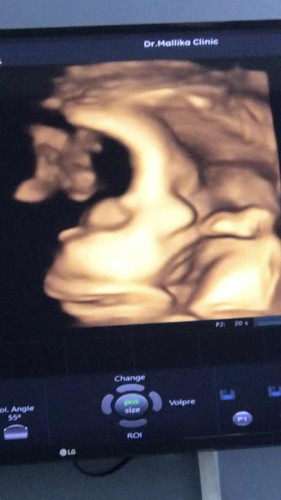

36+6week ทีมธันวา66 จะย้ายทีมมั้ยนะ

บ้านนี้ 36+3 คุณแม่เลือกผ่าคลอด ป้าหมอนัดผ่า 2/12/66 ครับ แต่หน่วงจิมิมาก แอบกลัวว่าจะมาก่อนกำหนดผ่าเหมือนกันค่ะ

36+5 นัดผ่าวันที่ 7 ธ.ค ค่ะ ท้องแข็งบ่อย ปวดหลังสุดๆ